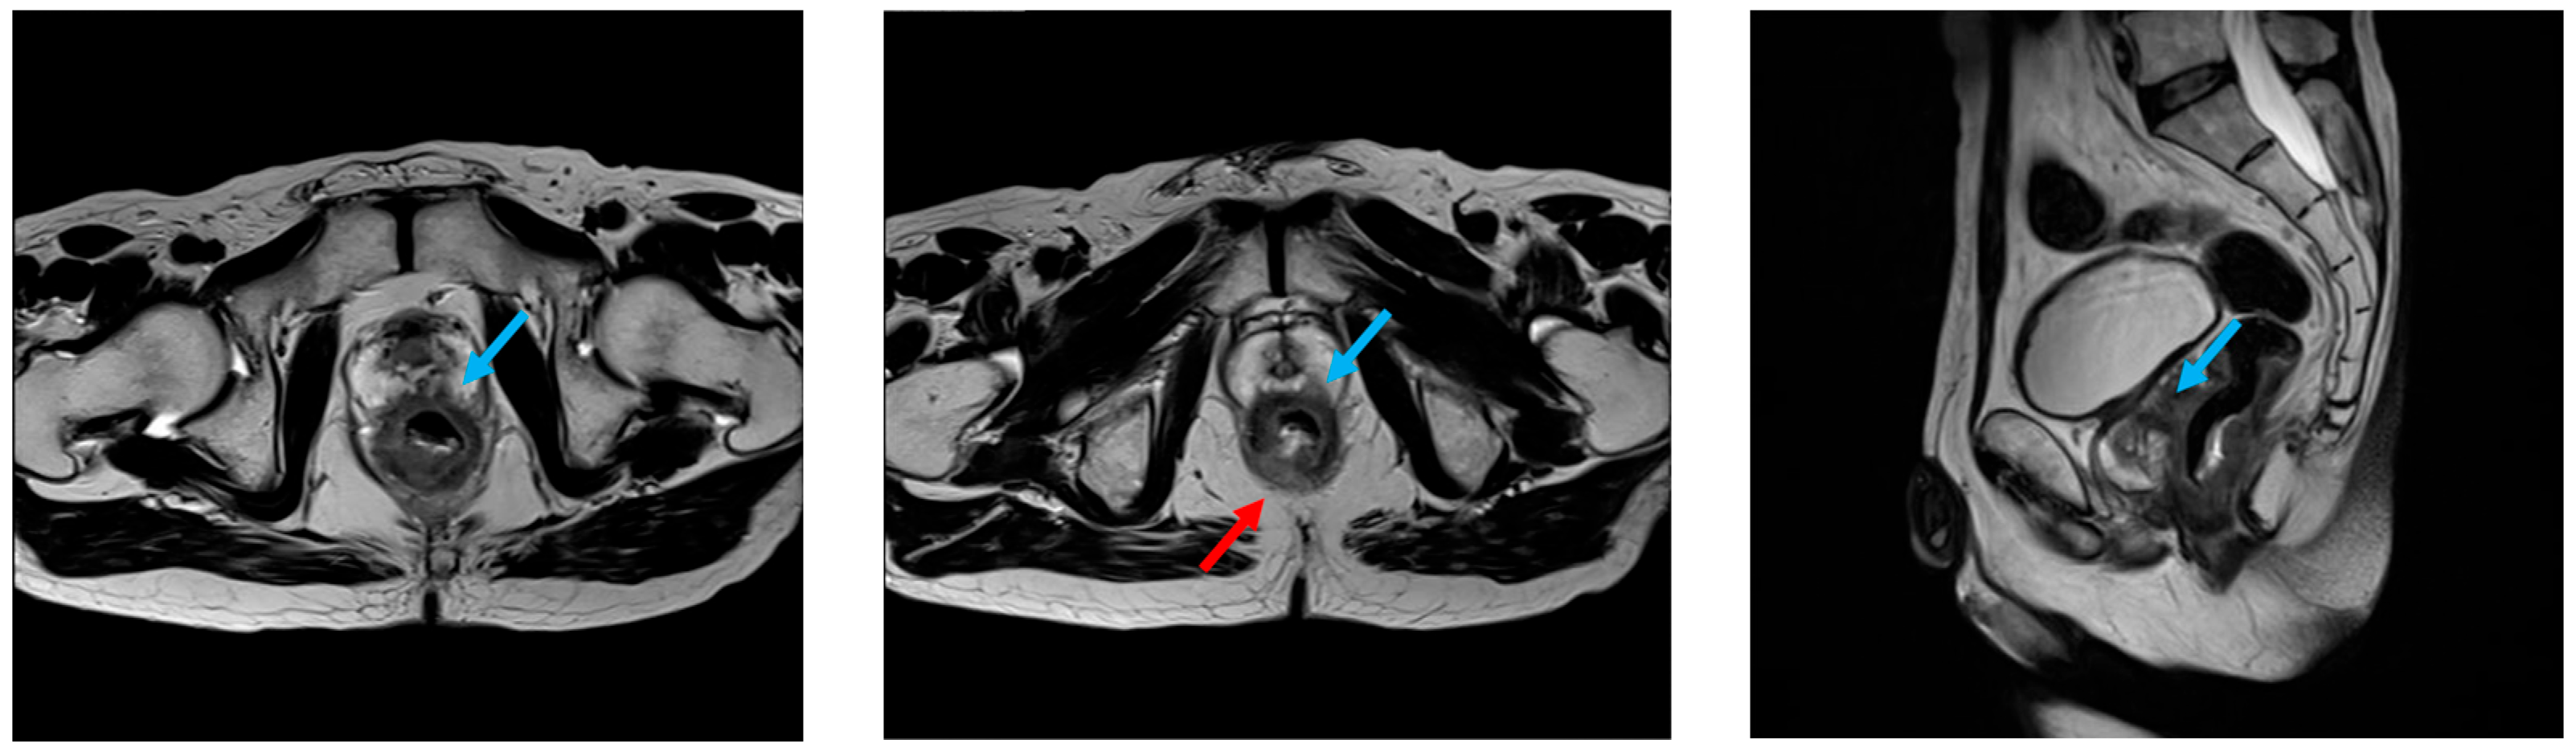

2.1. Patient

2.3. Surgical Procedure